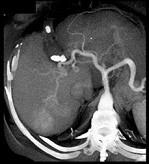

问题 男,44岁,患乙肝多年,现腹痛,腹胀,AFP增高,消瘦、乏力,影像检查如图,最可能诊断是 ( )

选项 A.肝血管瘤 B.肝腺瘤 C.肝转移瘤 D.肝硬化、肝癌 E.肝结节性增生

答案 D